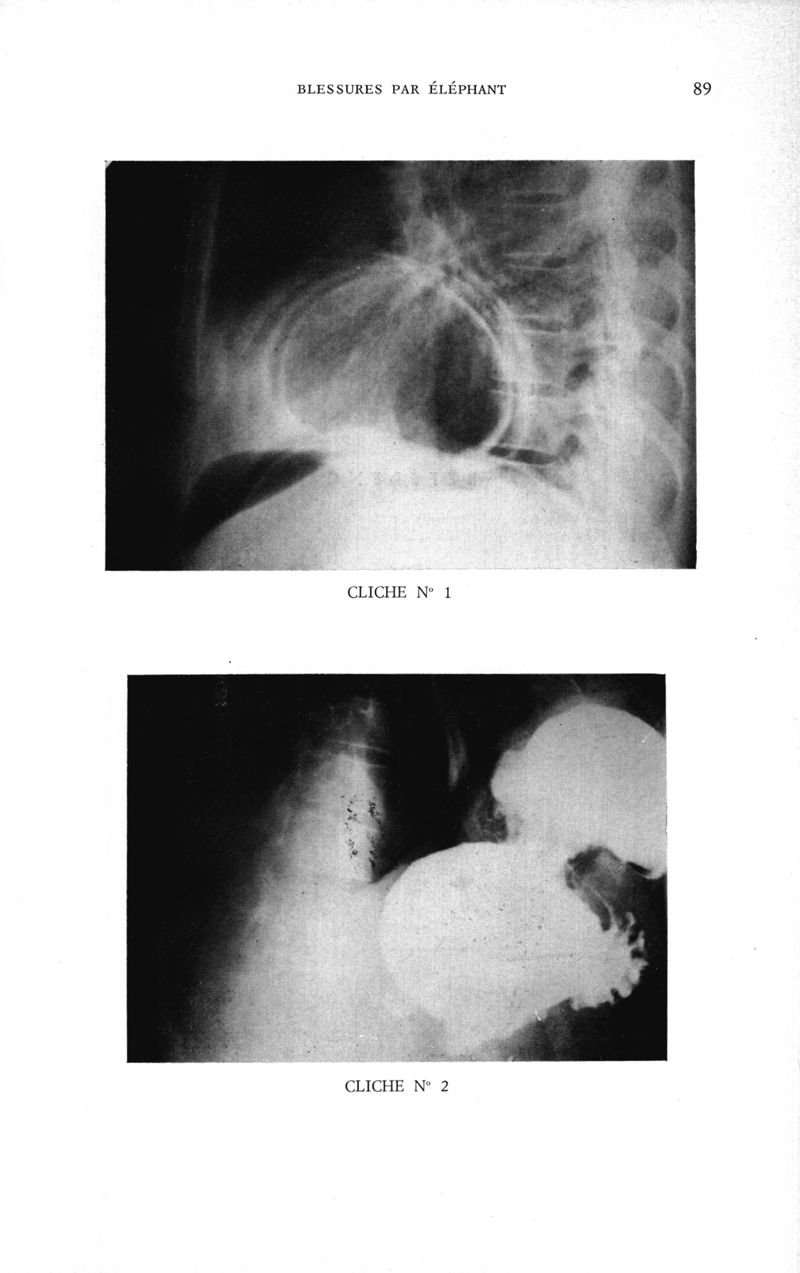

Médecine tropicale: revue française de pathologie et de santé publique tropicales

. - Marseille, 1974.